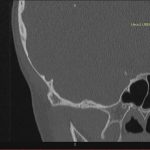

- Diagnosticul traumatismelor de bază de craniu

- Diagnosticul fracturilor:

-

- Unice

- Multiple

- Cu înfundare

- Complexe cranio-sinusale

- Complexe cranio-etmoidale

- Complexe cranio-orbitare

- Complexe cranio-faciale